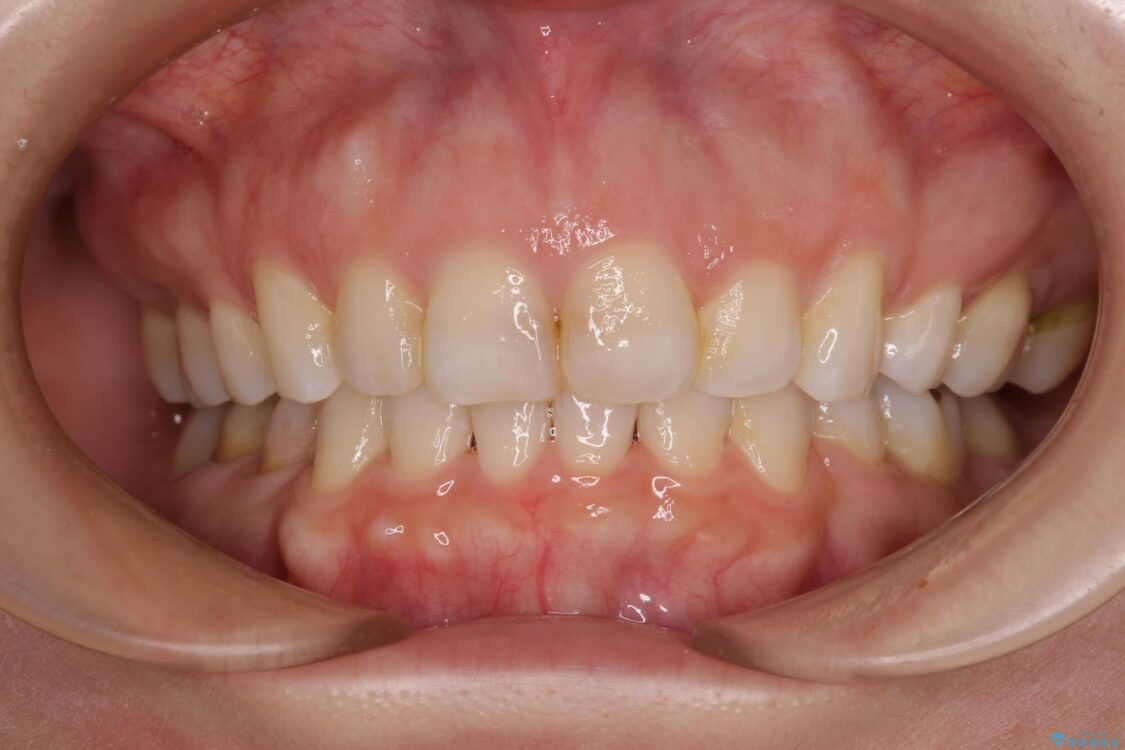

治療前

• 【モニター】出っ歯と咬み合わせを改善 ワイヤー装置の抜歯矯正 治療前画像